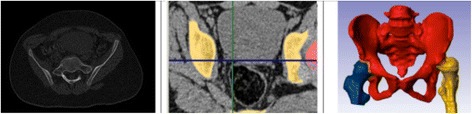

Pelvic models were generated using classic CT data obtained with the GE LightSpeed VCT 64-slice CT system (GE Healthcare, Little Chalfont, UK). Slice thickness of the accepted scans was <1.5 mm (0.63 or 1.25 mm). Scans formatted as DICOM files were transferred to ScanIP for processing of 3D images. The areas of the pelvic bones were marked on each scan. Based on this, the ScanIP algorithm generated a triangle-surface mesh describing the geometry of the analyzed pelvis. The accuracy of this process (segmentation) is crucial in obtaining quality 3D models (Figure 1). The resulting 3D model was subsequently exported to Rhinoceros, a specialized design software for measuring spatial images.

Figure 1.

The segmentation process in generating the 3D model of the pelvis.